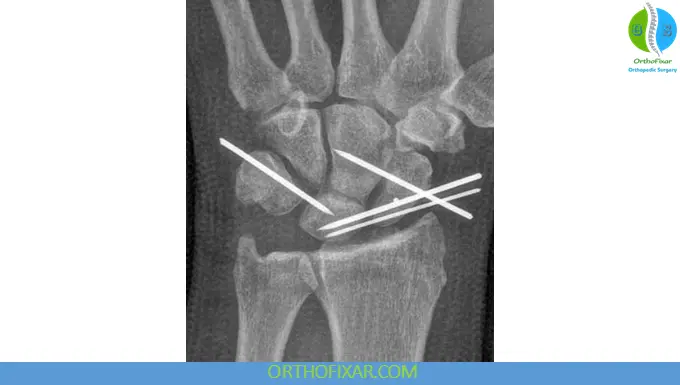

1. Arthroscopic Reduction and Pinning

- Minimally invasive

- Variable outcomes

- Suitable for early injuries

2. Open Reduction and Internal Fixation (ORIF)

Indicated when:

- Reduction cannot be achieved or maintained

Key steps:

- Dorsal surgical approach

- Reduction of scapholunate interval

- Repair of the scapholunate ligament (if possible)

- Dorsal capsulodesis

- Stabilization using Kirschner wires (K-wires)

Volar approach may be used when needed.